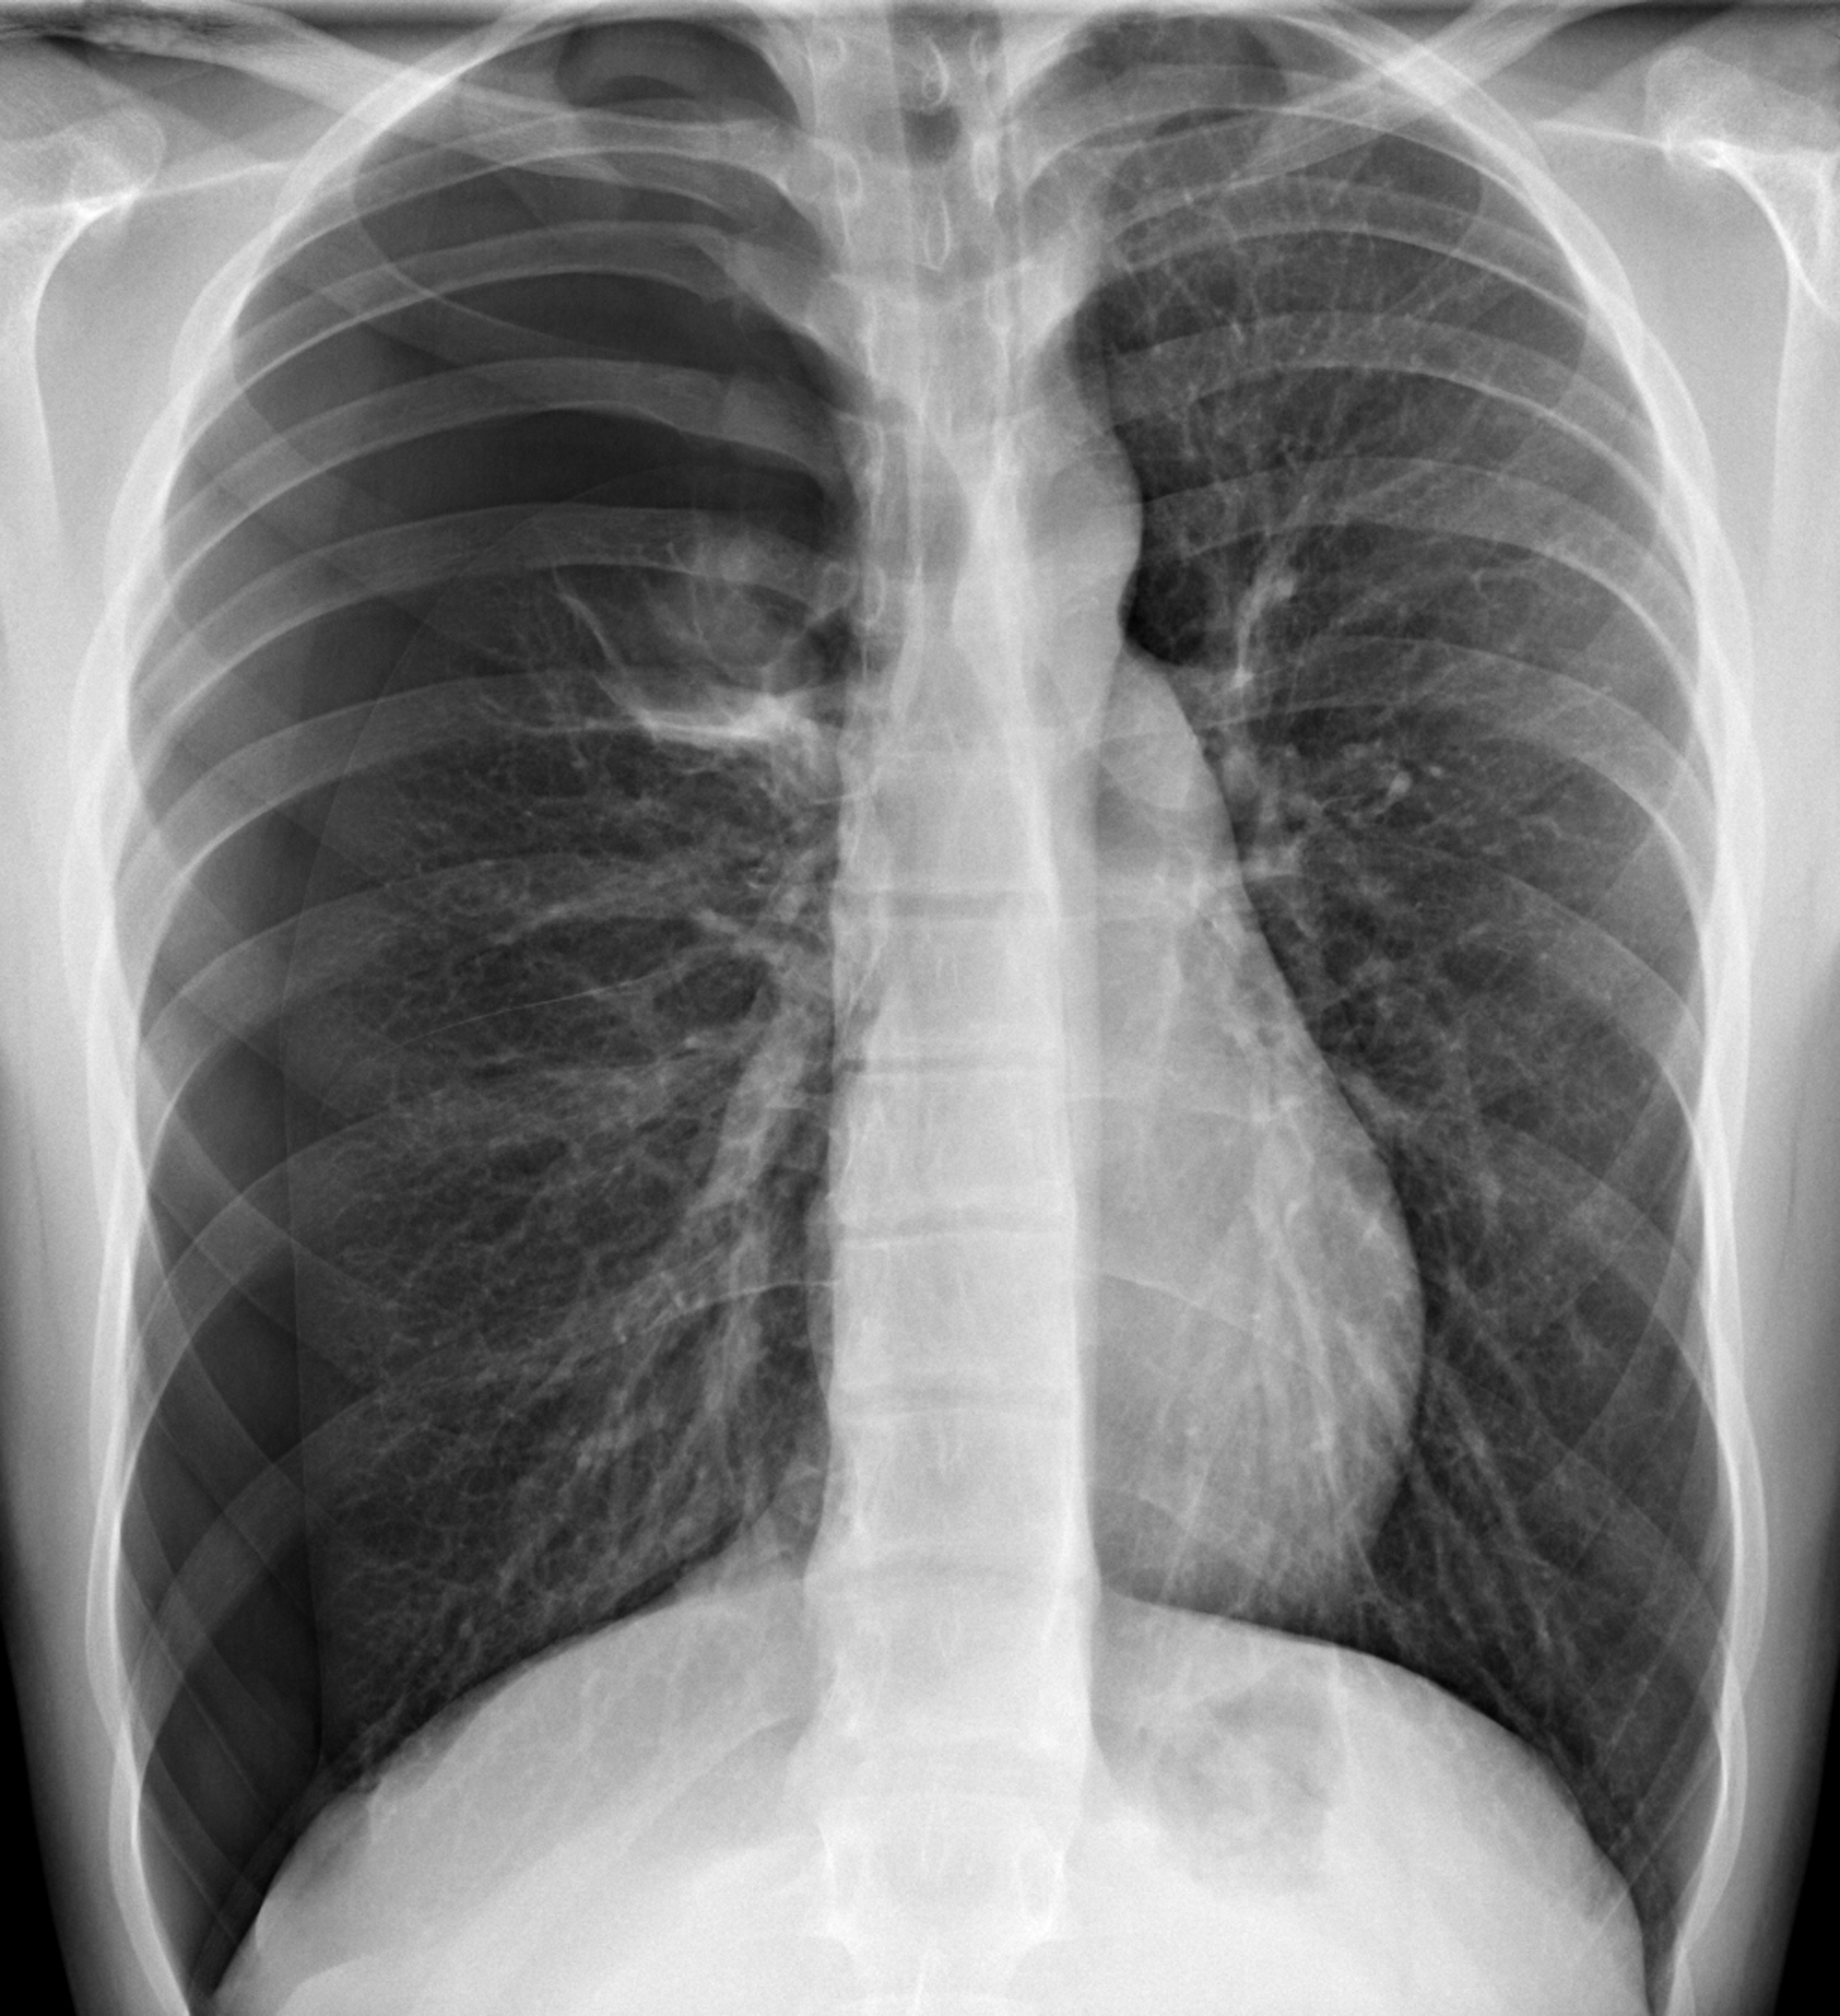

최근 진료를 보다가, 젊은 환자 분들중에 키가 크고 마른 학생들에게서 발견한 케이스입니다.

제가 본 학생은 신장(키)이 더 빠르게 생장하다 보면 폐 성장이 늦어지면서 그 빈 공간(흉막강)을 공기가 차게 되는 경우의 케이스였습니다. 폐와 흉각은 흉막이라는 막에 쌓여 있는데, 평소에는 공기 대신 흉막액이 있어야할 공간인 곳이죠. (자발성 기흉.)

흉통과 호흡곤란

자발성 기흉

- 일차성 자연기흉 : 기존에 폐질환이 없는 건강한 사람에서 발생한 기흉 (키가 크고 마른 사람, 흡연, 대기오염)